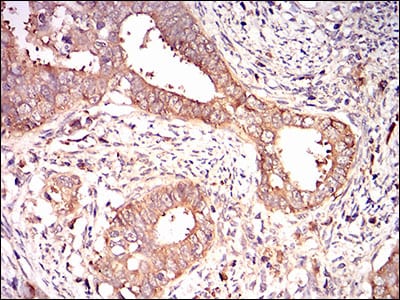

分类: 科研抗体货号: 30596别名:应用: WB,IHC,FCM反应种属: Human